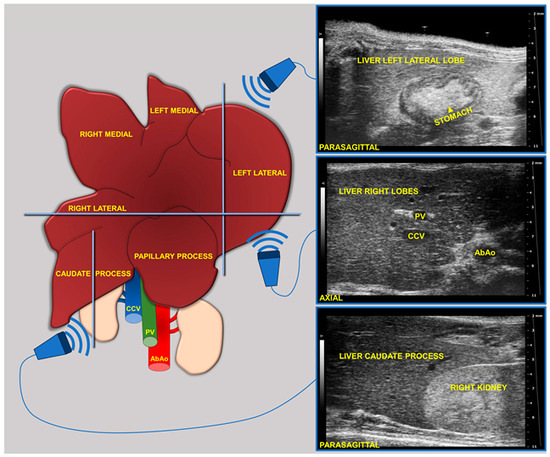

2.4.1. Ultrasound Acquisition

During imaging sessions, body temperature, heart, and breath rates were monitored and normothermia was maintained using a heated platform and an infrared lamp. Mice were anesthetized with inhalant gases (induction chamber: 4% isoflurane plus 2 Lt/min oxygen; maintenance with nose cone: 1.5–1.8% plus 2 Lt/min oxygen). Subsequently, the mice were placed in a supine position and a coupling gel was applied to the trichotomized skin. US two-dimensional (2D) B-mode images of the liver of mice (left, right, and caudate lobes, sagittal and axial planes) at 8 (baseline, pre-diet), 16, and 24 weeks of age were acquired in real time by a veterinary radiologist with 17 years of experience (SG) (

Figure 1). A dedicated HFUS equipment was used (Vevo 2100, FUJIFILM VisualSonics Inc., Toronto, ON, Canada; MS550 transducer: central frequency 40 MHz; focal length 6 mm; depth of penetration 5–15 mm; 30–40 µm axial and 70–90 µm lateral resolution). The time gain compensation and other operating parameters were kept constant throughout experiments (frequency = 40 MHz, frame rate = 16 images/s, gain = 30 dB, depth = 11 mm, width = 13.00 mm, dynamic range = 60 dB, sensitivity = high; transmit power = 100%) to avoid experimental bias. Each liver HFUS acquisition, including overall animal preparation, took no more than 15 min. During recovery, all animals were monitored for any signs of pain or discomfort.